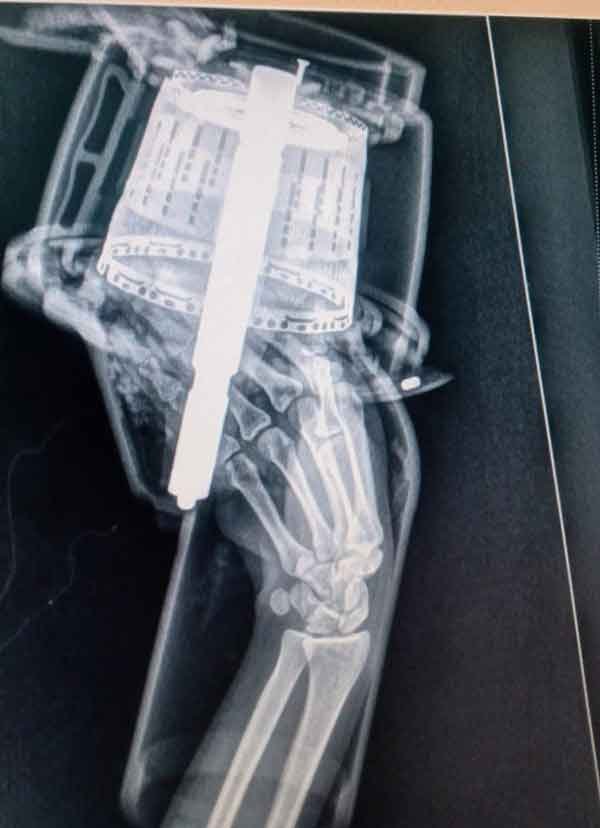

A vítima estava com o antebraço preso no equipamento, e alegava estar sentindo muita dor. A mulher foi conduzida pela equipe de resgate ao Hospital e Maternidade São José, onde recebeu sedação para que os bombeiros pudessem então efetuar a retirada do objeto, sem que houvesse maiores prejuízos à vítima.

Felizmente, no primeiro exame de raio X não constava fratura. Após a retirada do objeto, seria realizado um segundo raio X para verificar com precisão a existência ou não de lesões. A vítima ficou aos cuidados da equipe médica da unidade hospitalar.